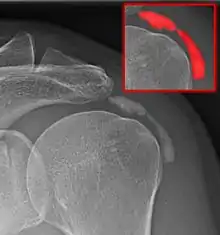

Calcific bursitis refers to calcium deposits within the bursae. This most occurs in the shoulder area. The most common bursa for calcific bursitis to occur is the subacromial bursa. A bursa is a small, fluid-filled sac that reduces friction, and facilitates movements between its adjacent tissues (i.e., between tendon and bone, two muscles or skin and bone). Inflammation of the bursae is called bursitis.

Diagnosis